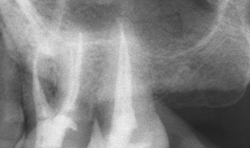

Canal measurement (m1) – The memory one mode (Fig. 6) allows for the electronic measurement of the root canal. The motor doesn’t rotate in this mode. With a lip clip applied to the corner of the mouth and file holder attached to the file in the root canal, the length can be determined (Fig. 7). As the file approaches the minor diameter or apical constriction, there’s an audible sound and the file position and overall length can be confirmed on the LCD display.

Fig. 7